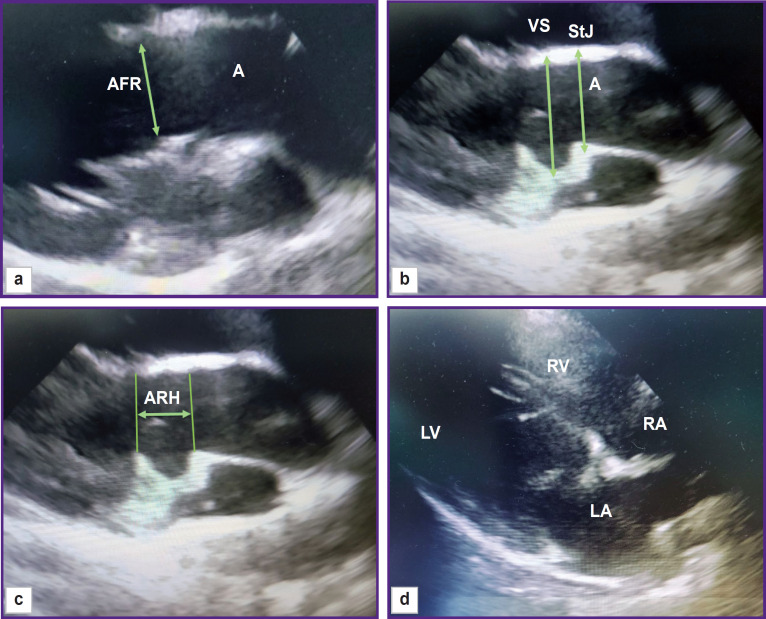

Materials and methods: The study was performed on 17 healthy crossbred Romanov sheep weighing 20-29 kg in group 1 (n=7) and 30-43 kg in group 2 (n=10). All animals underwent echocardiography examination on the Philips CX-50 apparatus (revision 3.1.2; Philips, Netherlands) with a sector-phased S5-1 sensor from the right parasternal projection (long and short axis) to determine the heart rate, right ventricular wall thickness in diastole, right and left ventricular end-diastolic dimensions (RV EDD and LV EDD), left ventricular end-systolic dimension (LV ESD), interventricular septum (IVS) thickness in systole and diastole, left ventricular posterior wall thickness in systole and diastole.Functional parameters of the left ventricle (left ventricle end-systolic and end-diastolic volumes (LV ESV and LV EDV), ejection fraction and shortening fraction) were calculated using the modified Simpson method built into the echocardiography software. The diameter of the mitral annulus and the characteristics of the aortic root were also measured: the diameters of the aortic valve, Valsalva sinuses, and sinotubular junction, as well as the height of the aortic root from the fibrous ring to the line of the sinotubular junction. Direct measurements of the ascending aorta and pulmonary artery diameters, intercommissural distances, and the height of the aortic valve leaflets were performed after autopsy.

Results: A number of anatomical and functional parameters of the sheep heart such as ejection fraction, myocardium thickness, LV EDD and LV ESD, aorta, and pulmonary artery diameters, have been established to be close to those of the human heart. At the same time, LV EDV and LV ESV of the sheep are significantly lower than in humans, even in relation to the body surface area, and the average mitral valve diameter is larger. Despite the same diameters of the aortic valve, Valsalva sinuses, and sinotubular junction, the structures of the ovine and human aortic roots are different: the sheep root features a smaller height and intercommissural distances of the cusps. In addition, some differences were found in the arrangement of the cusps in relation to the valve axis: the intercommissural distance of the right coronary leaflet was almost 2 times greater than the similar indicator of the left coronary leaflet.Most anatomical and functional parameters have not shown any correlation with the animals' body weight. Only in group 2, a significant positive correlation between body weight and the height of the aortic valve leaflets was found.